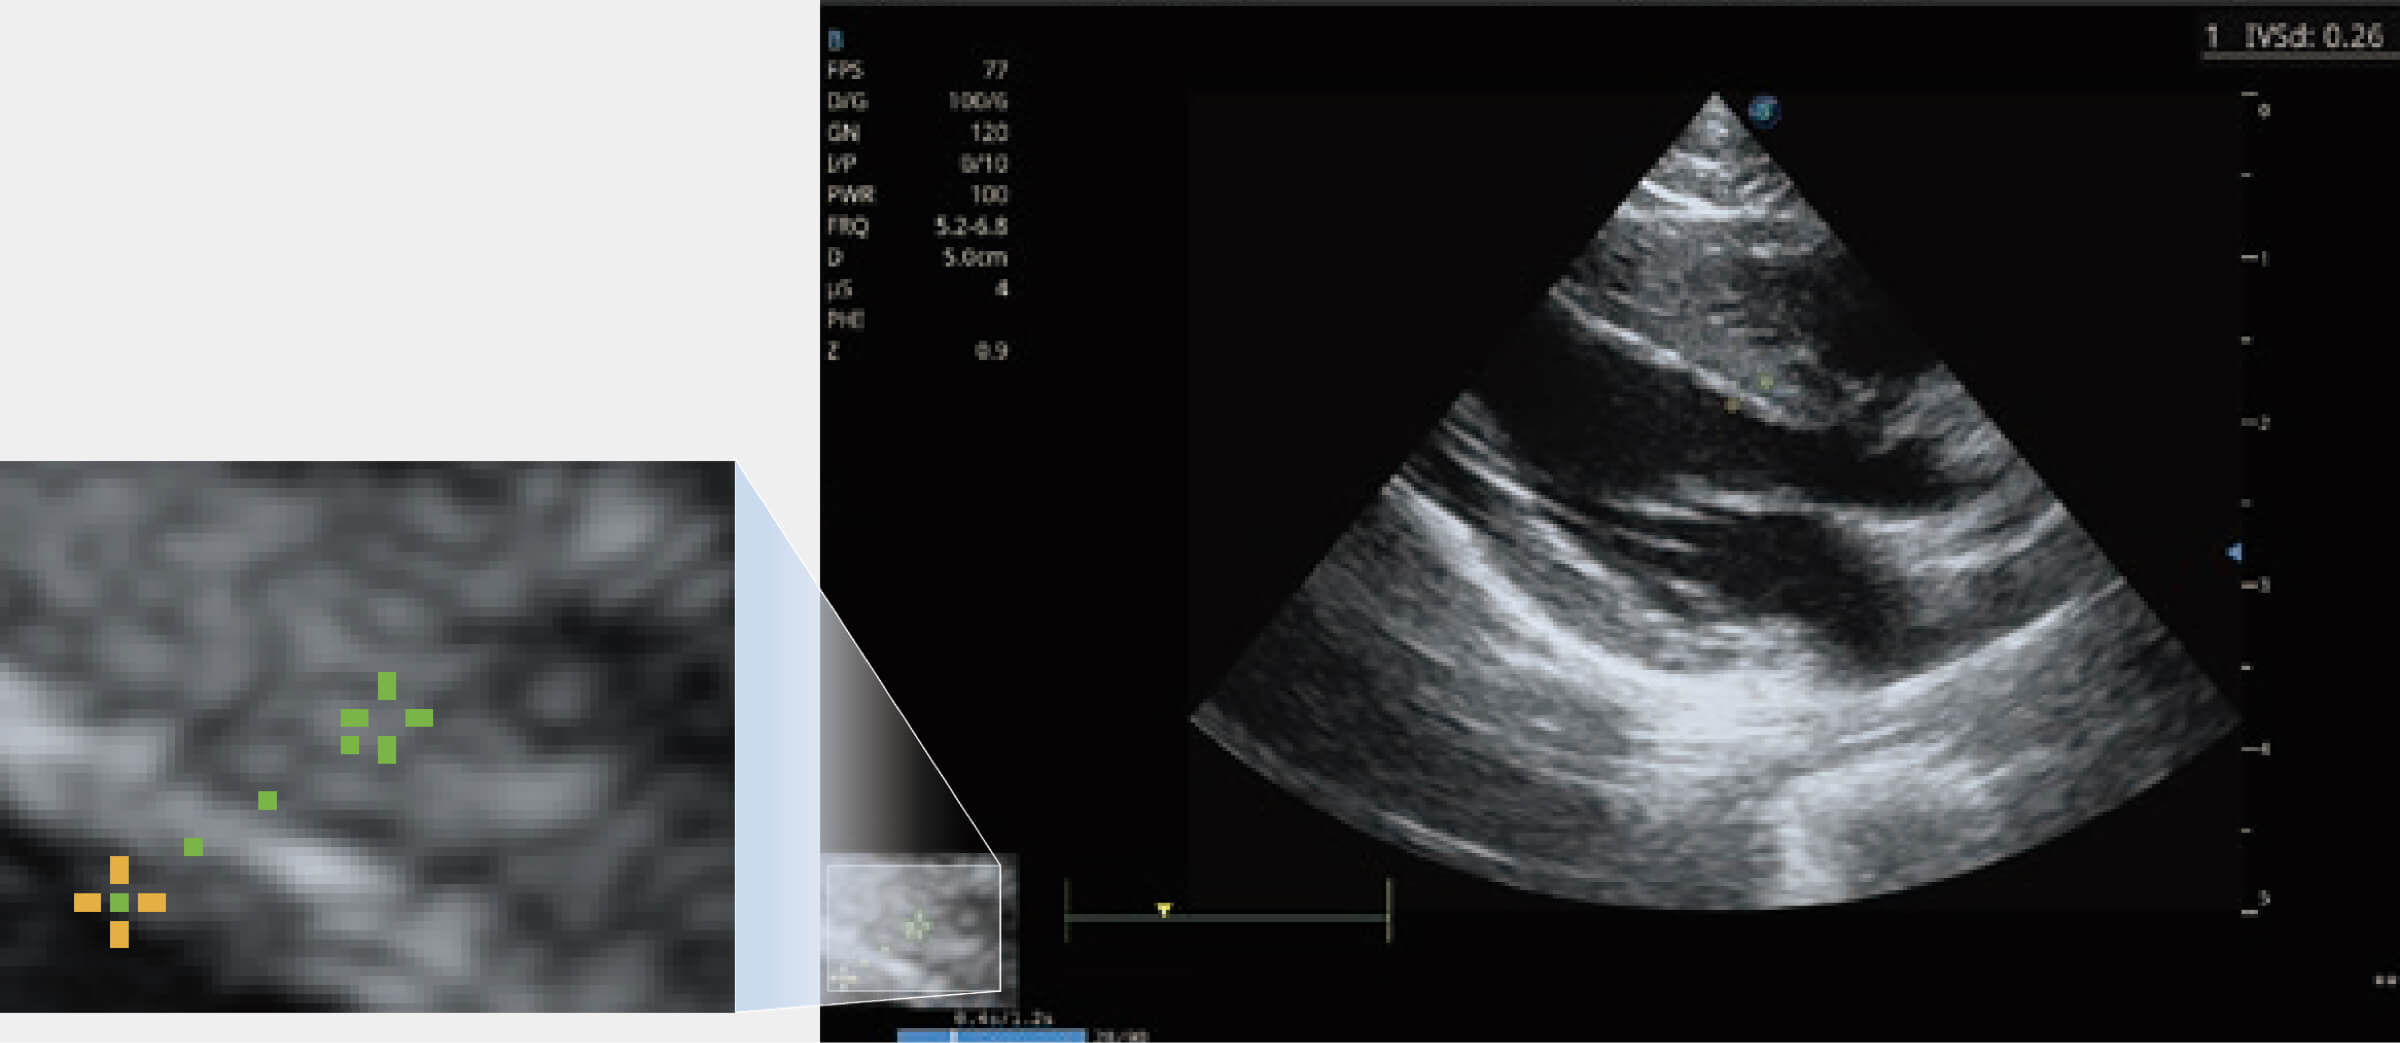

能夠基于左心室壁追蹤和辛普森法,自動(dòng)計(jì)算射血分?jǐn)?shù),支持多個(gè)可移動(dòng)點(diǎn)描跡,與手動(dòng)測量相比,極大節(jié)省了動(dòng)物醫(yī)生的時(shí)間和精力。

通過360度任意調(diào)節(jié)3條M型取樣線,在同一心動(dòng)周期上觀察心臟不同位置的運(yùn)動(dòng)曲線,得到準(zhǔn)確的心功能測量數(shù)據(jù),有效評估心肌運(yùn)動(dòng)及左心室功能。

實(shí)時(shí)用顏色表示心肌組織運(yùn)動(dòng),觀察和定量組織的運(yùn)動(dòng)情況,對快速檢測與評估心肌的灌注和活性、電傳導(dǎo)及心肌收縮和舒張功能等均能提供重要的診斷信息。